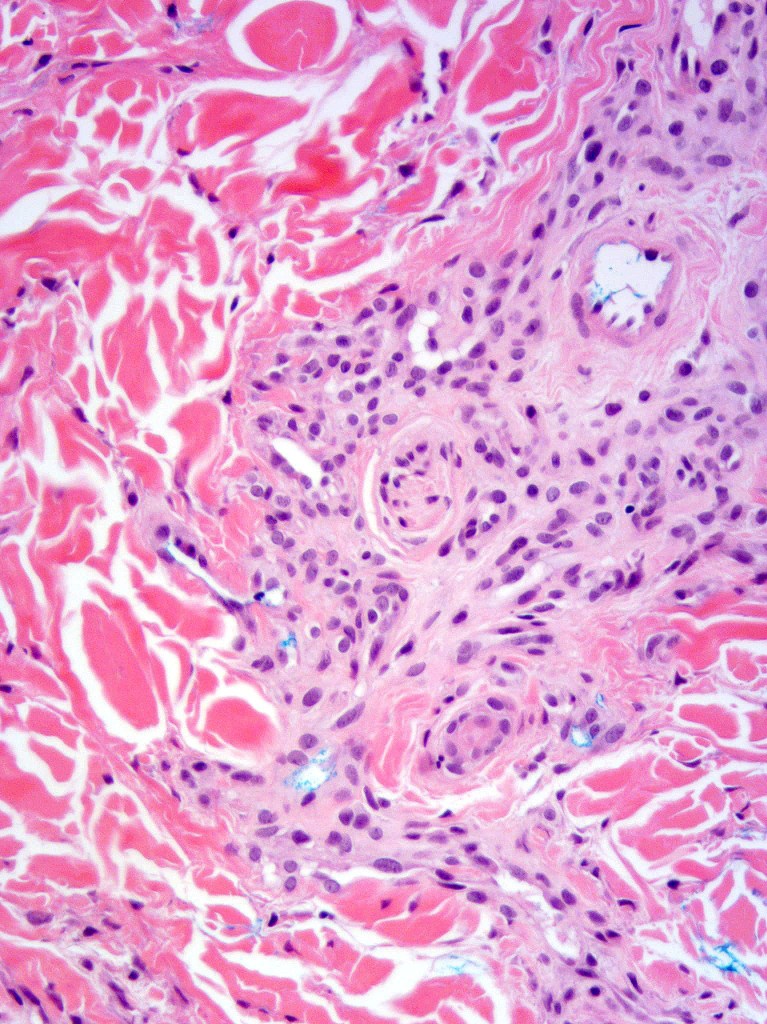

Histological features

•Mid- to deep dermal lobular infiltrate of sweat glands & ducts accompanied by capillaries & small vessels

•In some cases, larger venules & veins are present & associated arteriovenous malformation, spindle cell hemangioma, angiokeratoma & verrucous hemangioma have been described

•Variable myxoid change & mucin deposition